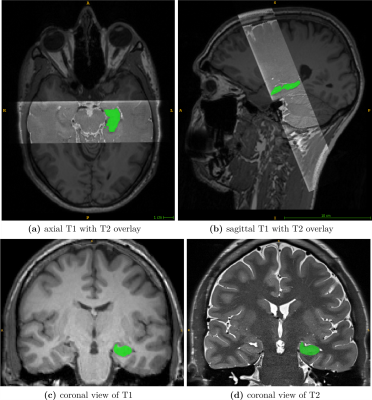

A unique dataset was acquired to create highly accurate GT segmentations for training the neural network and establishing reference data to evaluate the performance of FreeSurfer v7.3.2. Twenty-three healthy volunteers were scanned at a Siemens Prisma 3T MR scanner to obtain corresponding pairs of high-resolution T1 and T2 images (see Figure 2).

Figure 2: Representative MR-dataset for GT generation. Subfigures (a)/(b) show the axial/sagittal view of a T1 scan overlayed with the corresponding T2 slab. (c) depicts a coronal slice of an original T1 image. (d) shows an oblique coronal slice of the T2 slab. In all subfigures, the ground truth mask of the left hippocampus is displayed in green.